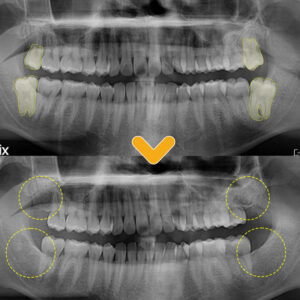

9. 수암동치과 임플란트 잘 하는 곳 찾고 계신가요?

수암동치과 임플란트 잘 하는 곳 찾고 계신가요? 안녕하세요. 모든 진료에 진심을 다하는 곳, 더플러스치과입니다. ​ 적지 않은 분들이 평소 구강 관리에 소홀하여 잇몸에 염증이 생겨 치주질환으로 치과를 찾으시곤 하는데요. 치주질환은 치아의 상실을 일으키는 주된 원인이기도 하며, 이는 잇몸과 치아 사이 틈의 치태가 제대로 제거되지 않아 쌓이고 굳어 생긴 치석으로 인해 더보기…